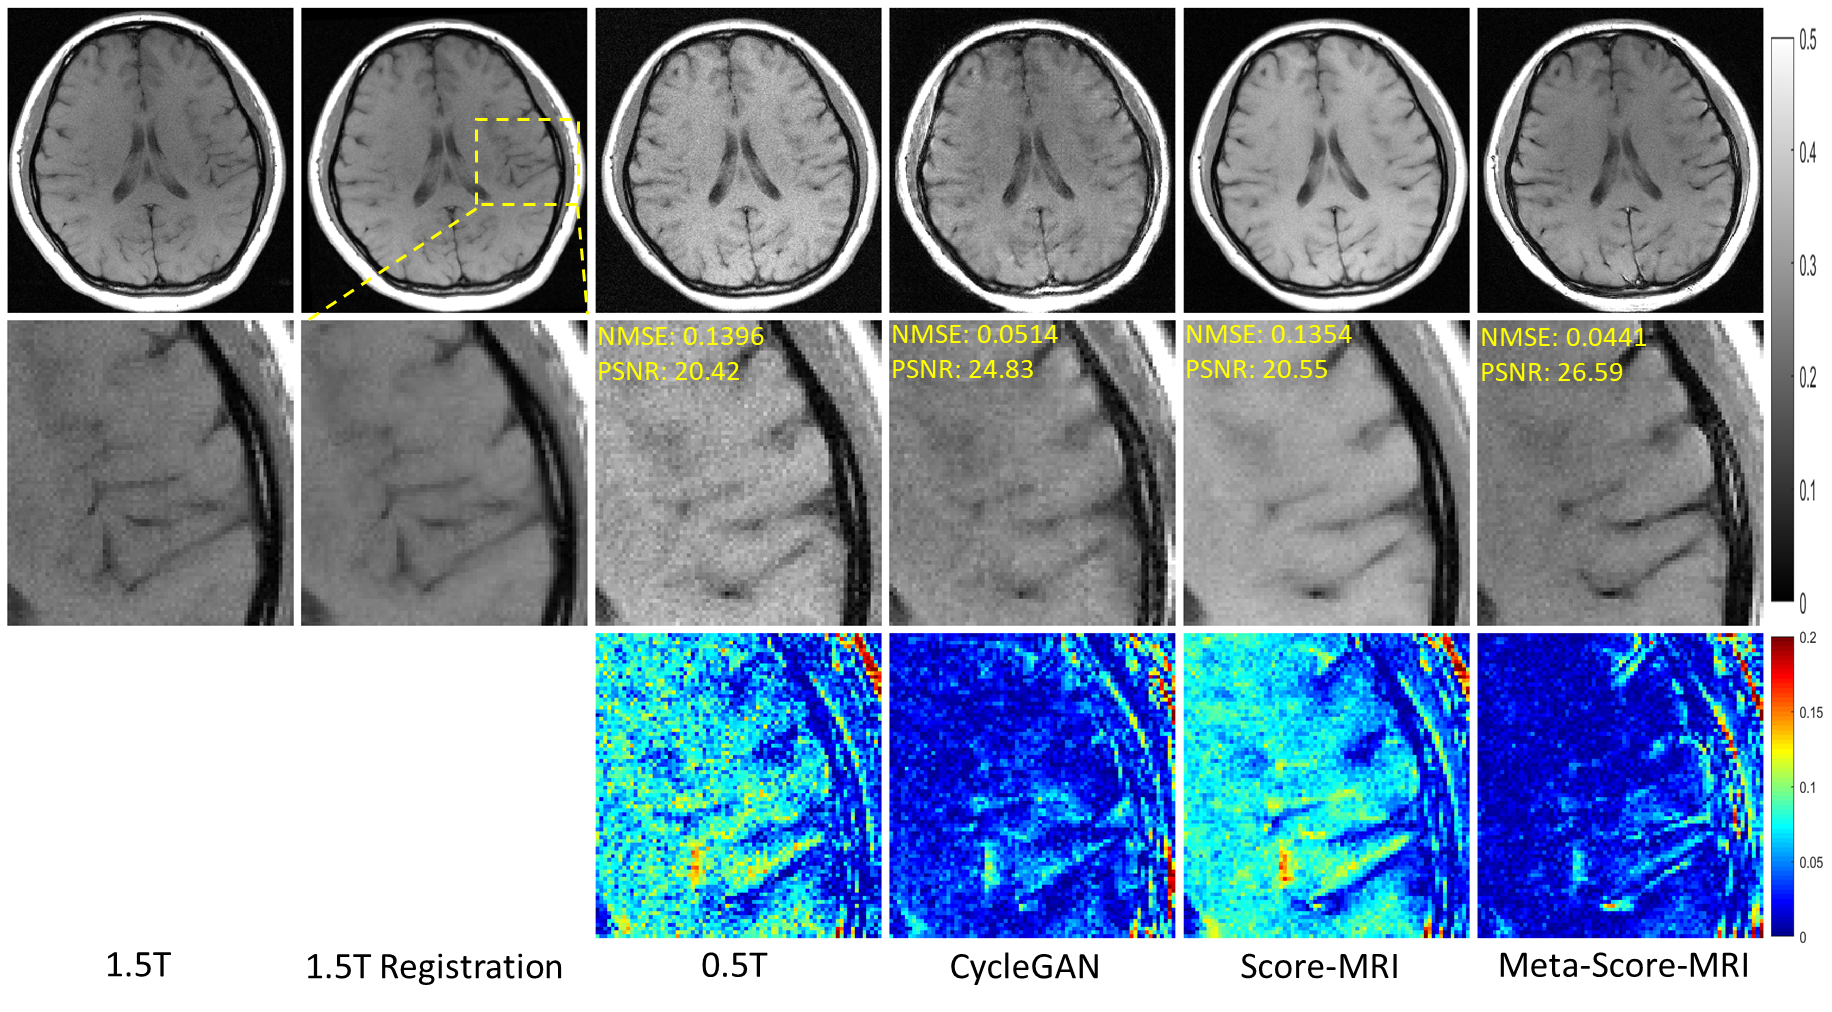

The results of different methods for reconstructing 1.5T T1W images are presented in Figure 4. It is evident that the image reconstructed by CycleGAN displays grid-like artifacts. While Score-MRI performs consistently with the previous experiment by enhancing the image’s SNR, the contrast level remains at that of a 0.5T level. Additionally, the sulcus region of the Score-MRI outcome appeared blurred. In contrast, the proposed method shows a significant improvement in both contrast and SNR, resulting in a clear reconstruction in the sulcus region that matches the quality of 1.5T T1W images.

Refer to caption

Figure 4: Reconstruction of 1.5T-like T1W MR Images from full-sampled 0.5T T1W MRI. The first line showcases the original 1.5T MR image, while the second line demonstrates the registration of the 1.5T image with the shape of the 0.5T MR image. The third line showcases the 0.5T MR image. The resulting reconstructed images are depicted in lines four through six. On the other hand, the second row offers an enlarged view, and the third row shows the error view between the generated 1.5T-like image and the registered 1.5T image. The NMSE/PSNR values of the enlarged view are displayed in the corners. The grayscale of the reconstructed images is visible on the right side of the figure.